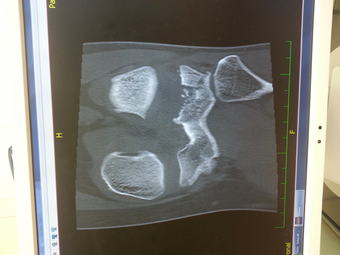

Je to CT a vidíme zlomenou malou kost přímo pod kolenním kloubem. Vytrestal mě drop, došlápl jsem si na tu nohu plnou váhou.

Co to vidíme na tom rentgenu?

V pondělí artroskopie. Zlomený kousek kosti pod kolenním kloubem a utržený náhradní křížový vaz, který mi dělali cca 10 let zpátky. 2 měsíce nesmím na nohu došlápnout.

Aha jasny. Ja pochopila ze te vypakovali s ortezouB-) Na CT skoro nic videt neni. Bacha na poskozeni menisku a chrupavek. Operace je sice opeuz ale minimalne urci presnou diagnozu i kdyby nic nedelali. Ani mr nevidi vse. Mam s tim uz 2× osobni zkusenost